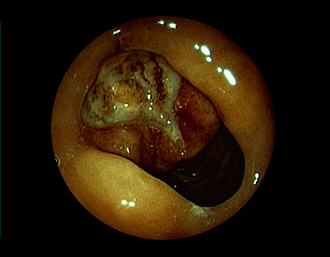

症例5:胃腺腫(84才女性)

胃角部に、大きさ10mm強のなだらかな粘膜隆起を認める。生検:Tubularadenoma with moderate atypia.Group 3。経過観察中。

(通常画像)